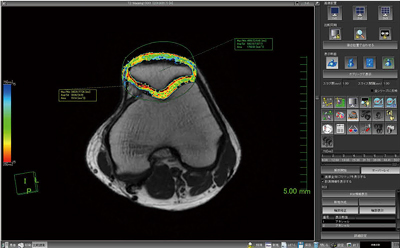

8.T2 Mapping

膝関節などの関節軟骨の変性に有用なソフトウェアとして,“T2 Mapping”を開発した。軟骨のT2値は,コラーゲン配列の変化や水分含有量などによって変化する。このT2値の変化をマルチエコーシーケンスによってとらえ,画素値の変化からT2値を算出することが可能である。変形性関節症の診断に,非常に有用なソフトウェアである(図10)。

図10 T2 Mapping